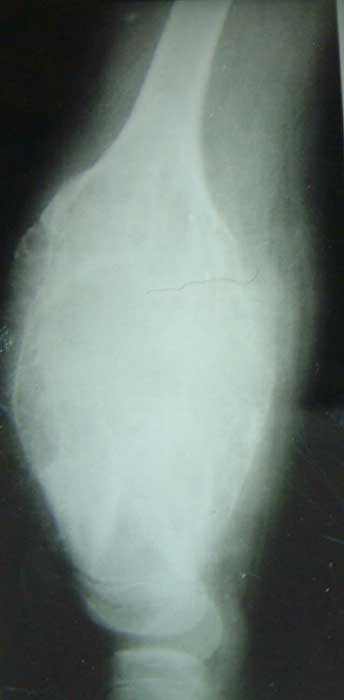

股骨远端骨母细胞瘤        段截肿瘤,大段异体骨移植术后3年愈合良好